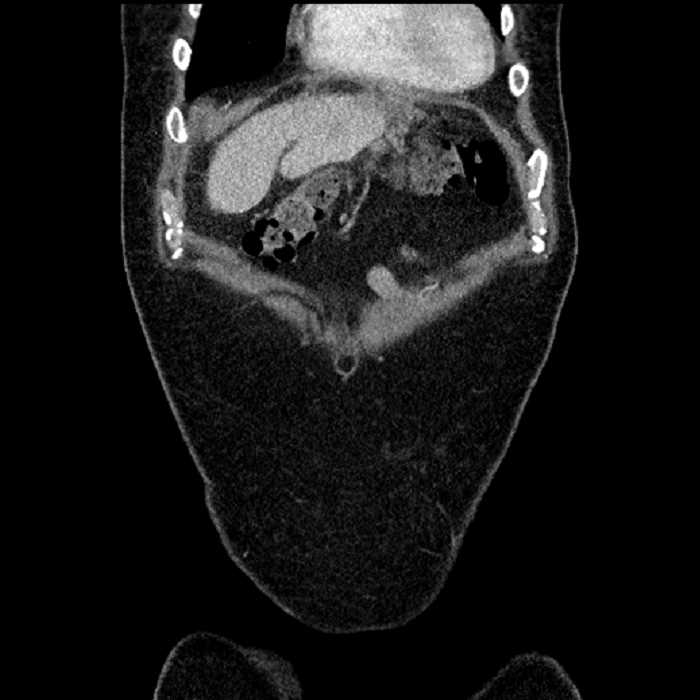

Age: 63

Sex: Male

Indication: Abdominal pain

• Large fluid density structure in hepatic segments 7 and 8 measuring 10 x 7 x 7 cm with internal septation and circumferential ill-defined low density compatible with edema

• Peripherally enhancing subcapsular collections along the anterior margin of the left hepatic lobe measuring 3 x 1 cm and 2 x 1 cm

• Clearly marginated fluid density structure in segment 7 and several other scattered tiny hypodensities, which likely represent cysts

• Hepatic abscess

Acute sigmoid diverticulitis complicated by a small contained perforation and a large abscess in the right hepatic lobe. Additional small subcapsular abscesses along the anterior margin of the left hepatic lobe.

Additionally, loss of the normal fat plane between the peridiverticular collection and adjacent thickened loops of small bowel raises the potential for an enterocolonic fistula.

• The classic CT imaging appearance is a double target sign with internal low density surrounded by an internal enhancing rim (capsule) and a low density external rim (edema)

Hepatic abscess showing the double target sign with low density internally surrounded by a thin inner enhancing rim (red arrow) and ill-defined outer low density rim (yellow arrow). Blue arrow indicates an internal septation. Red arrows: additional smaller subcapsular abscesses. Red arrow: focal contained perforation associated with diverticulitis.